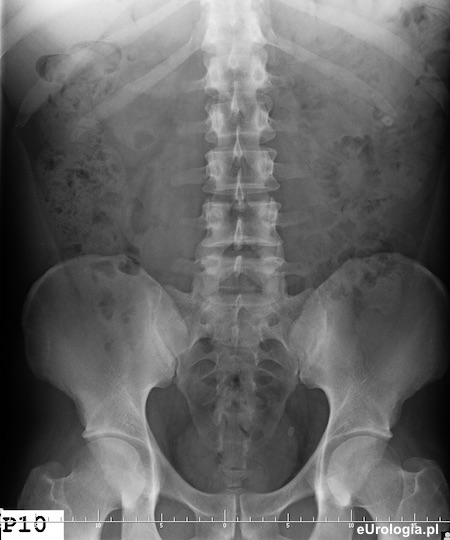

Zdjęcie przeglądowe jamy brzusznej. Widoczny cień wapienny w miednicy małej po stronie lewej o wymiarach 10x7 milimetrów